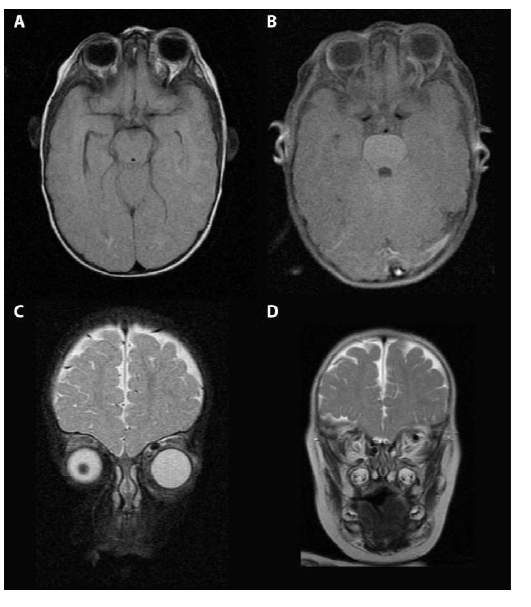

Niño, 12 meses, pretérmino, bajo peso, antecedente de traumatismo facial leve. Exoftalmos y quemosis de ojo izquierdo.Se realiza Resonancia Nuclear Magnética (RNM) cráneo que muestra dilatación de la vena oftálmica izquierda y proptosis de ojo izquierdo(Figura 1).

Figura1: RNMA) FLAIR axial. B) T1 FAT SAT axial. Donde se observa dilatación de la vena oftálmica superior y proptosis izquierda. C) T2 coronal. D)STIR coronal. Se evidencia dilatación de la vena oftálmica superior izquierda.